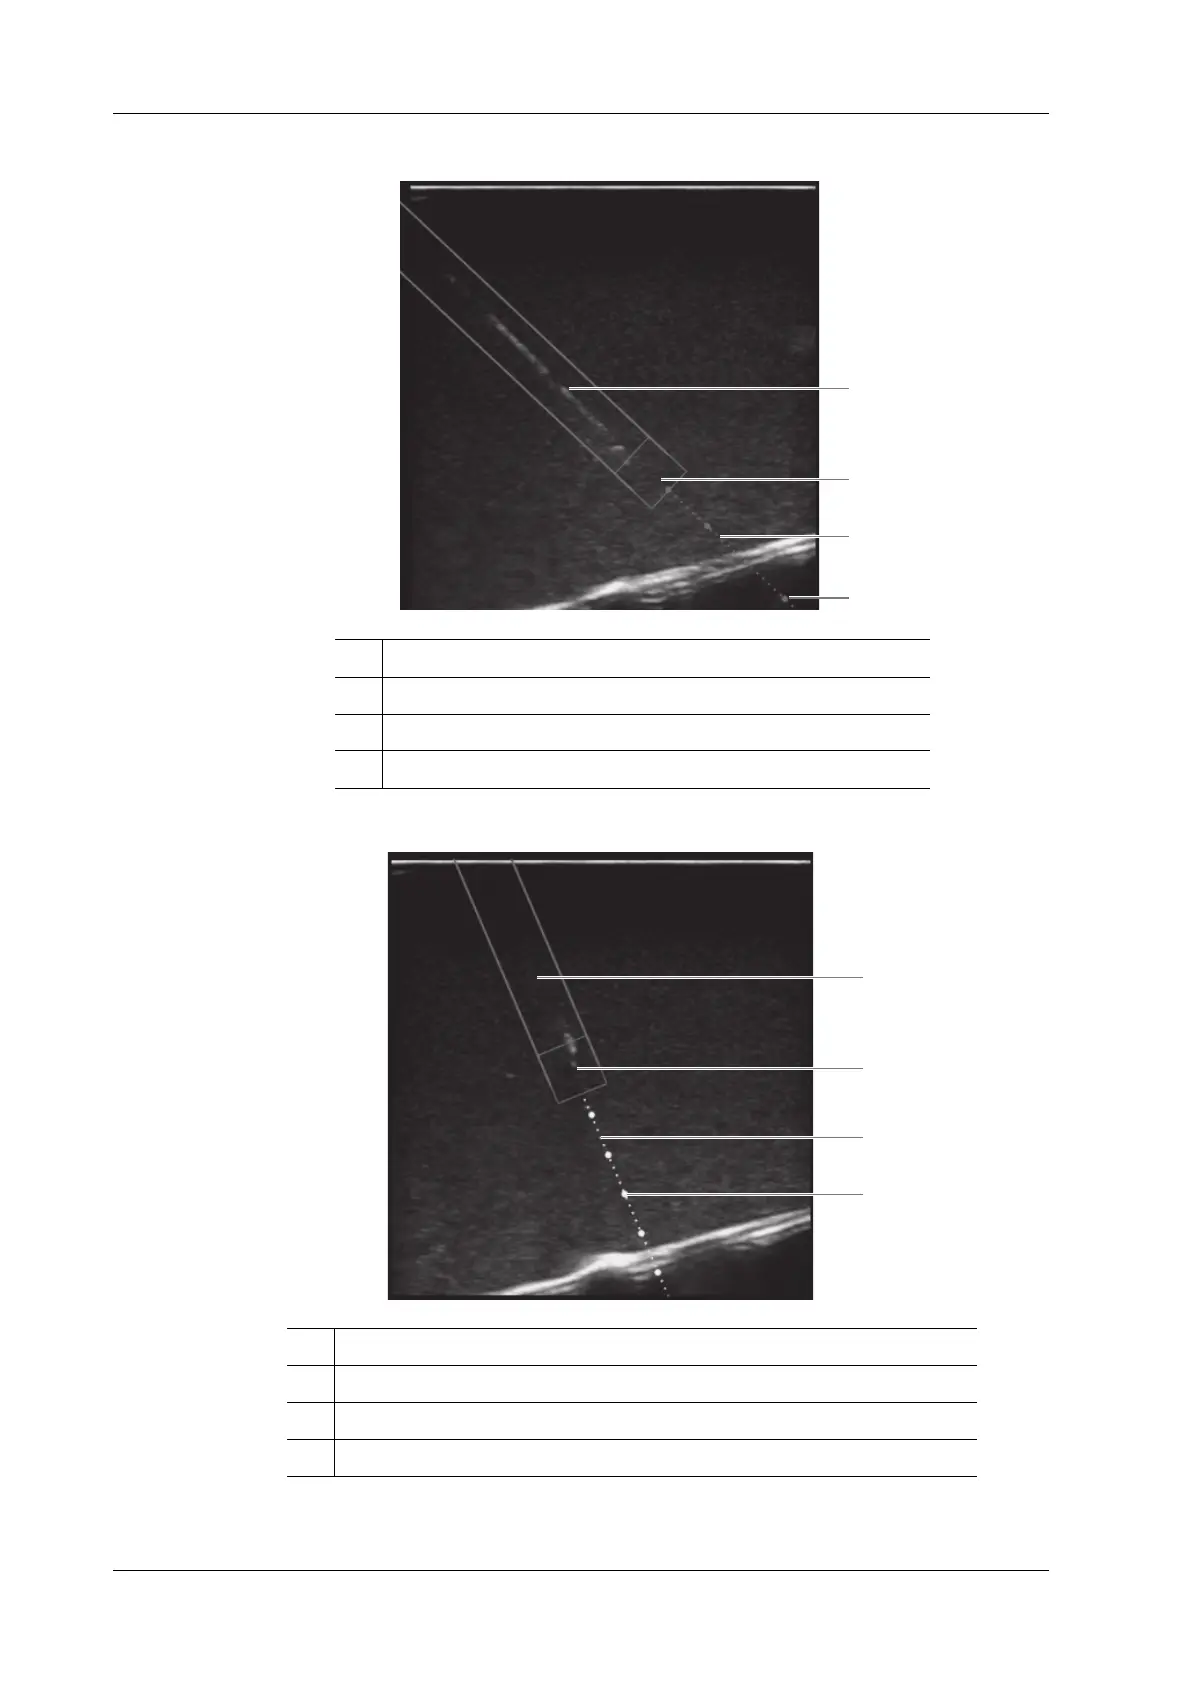

In Plane Needle Guidance GUI

Out of Plane Needle Guidance GUI

1 Needle position in the ultrasound plane

2 Needle tip position in the ultrasound plane

3 Needle guidance trajectory

4 Scale of guideline (5 mm/scale)

1 Needle projection position in the ultrasound plane

2 Position at which the needle cross the ultrasound plane

3 Projection position of the needle guidance trajectory in the ultrasound plane

4 Scale of guideline (5mm/scale)